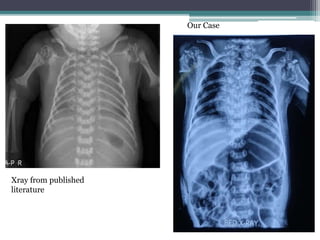

Xray Findings :

•Punctate calcification

•Metaphyseal splaying

• Thoracic Vertebral

segmentation defect

•Normal ribs scapulae

clavicle

•Normal

mineralization

Our case

Xray from published

literature

Vertebral Coronal Clefts

•Failure of fusion of

anterior and posterior

ossification centers

•Best seen on lateral

Xray films

•Radiolucent band

running through the

vertebral bodies